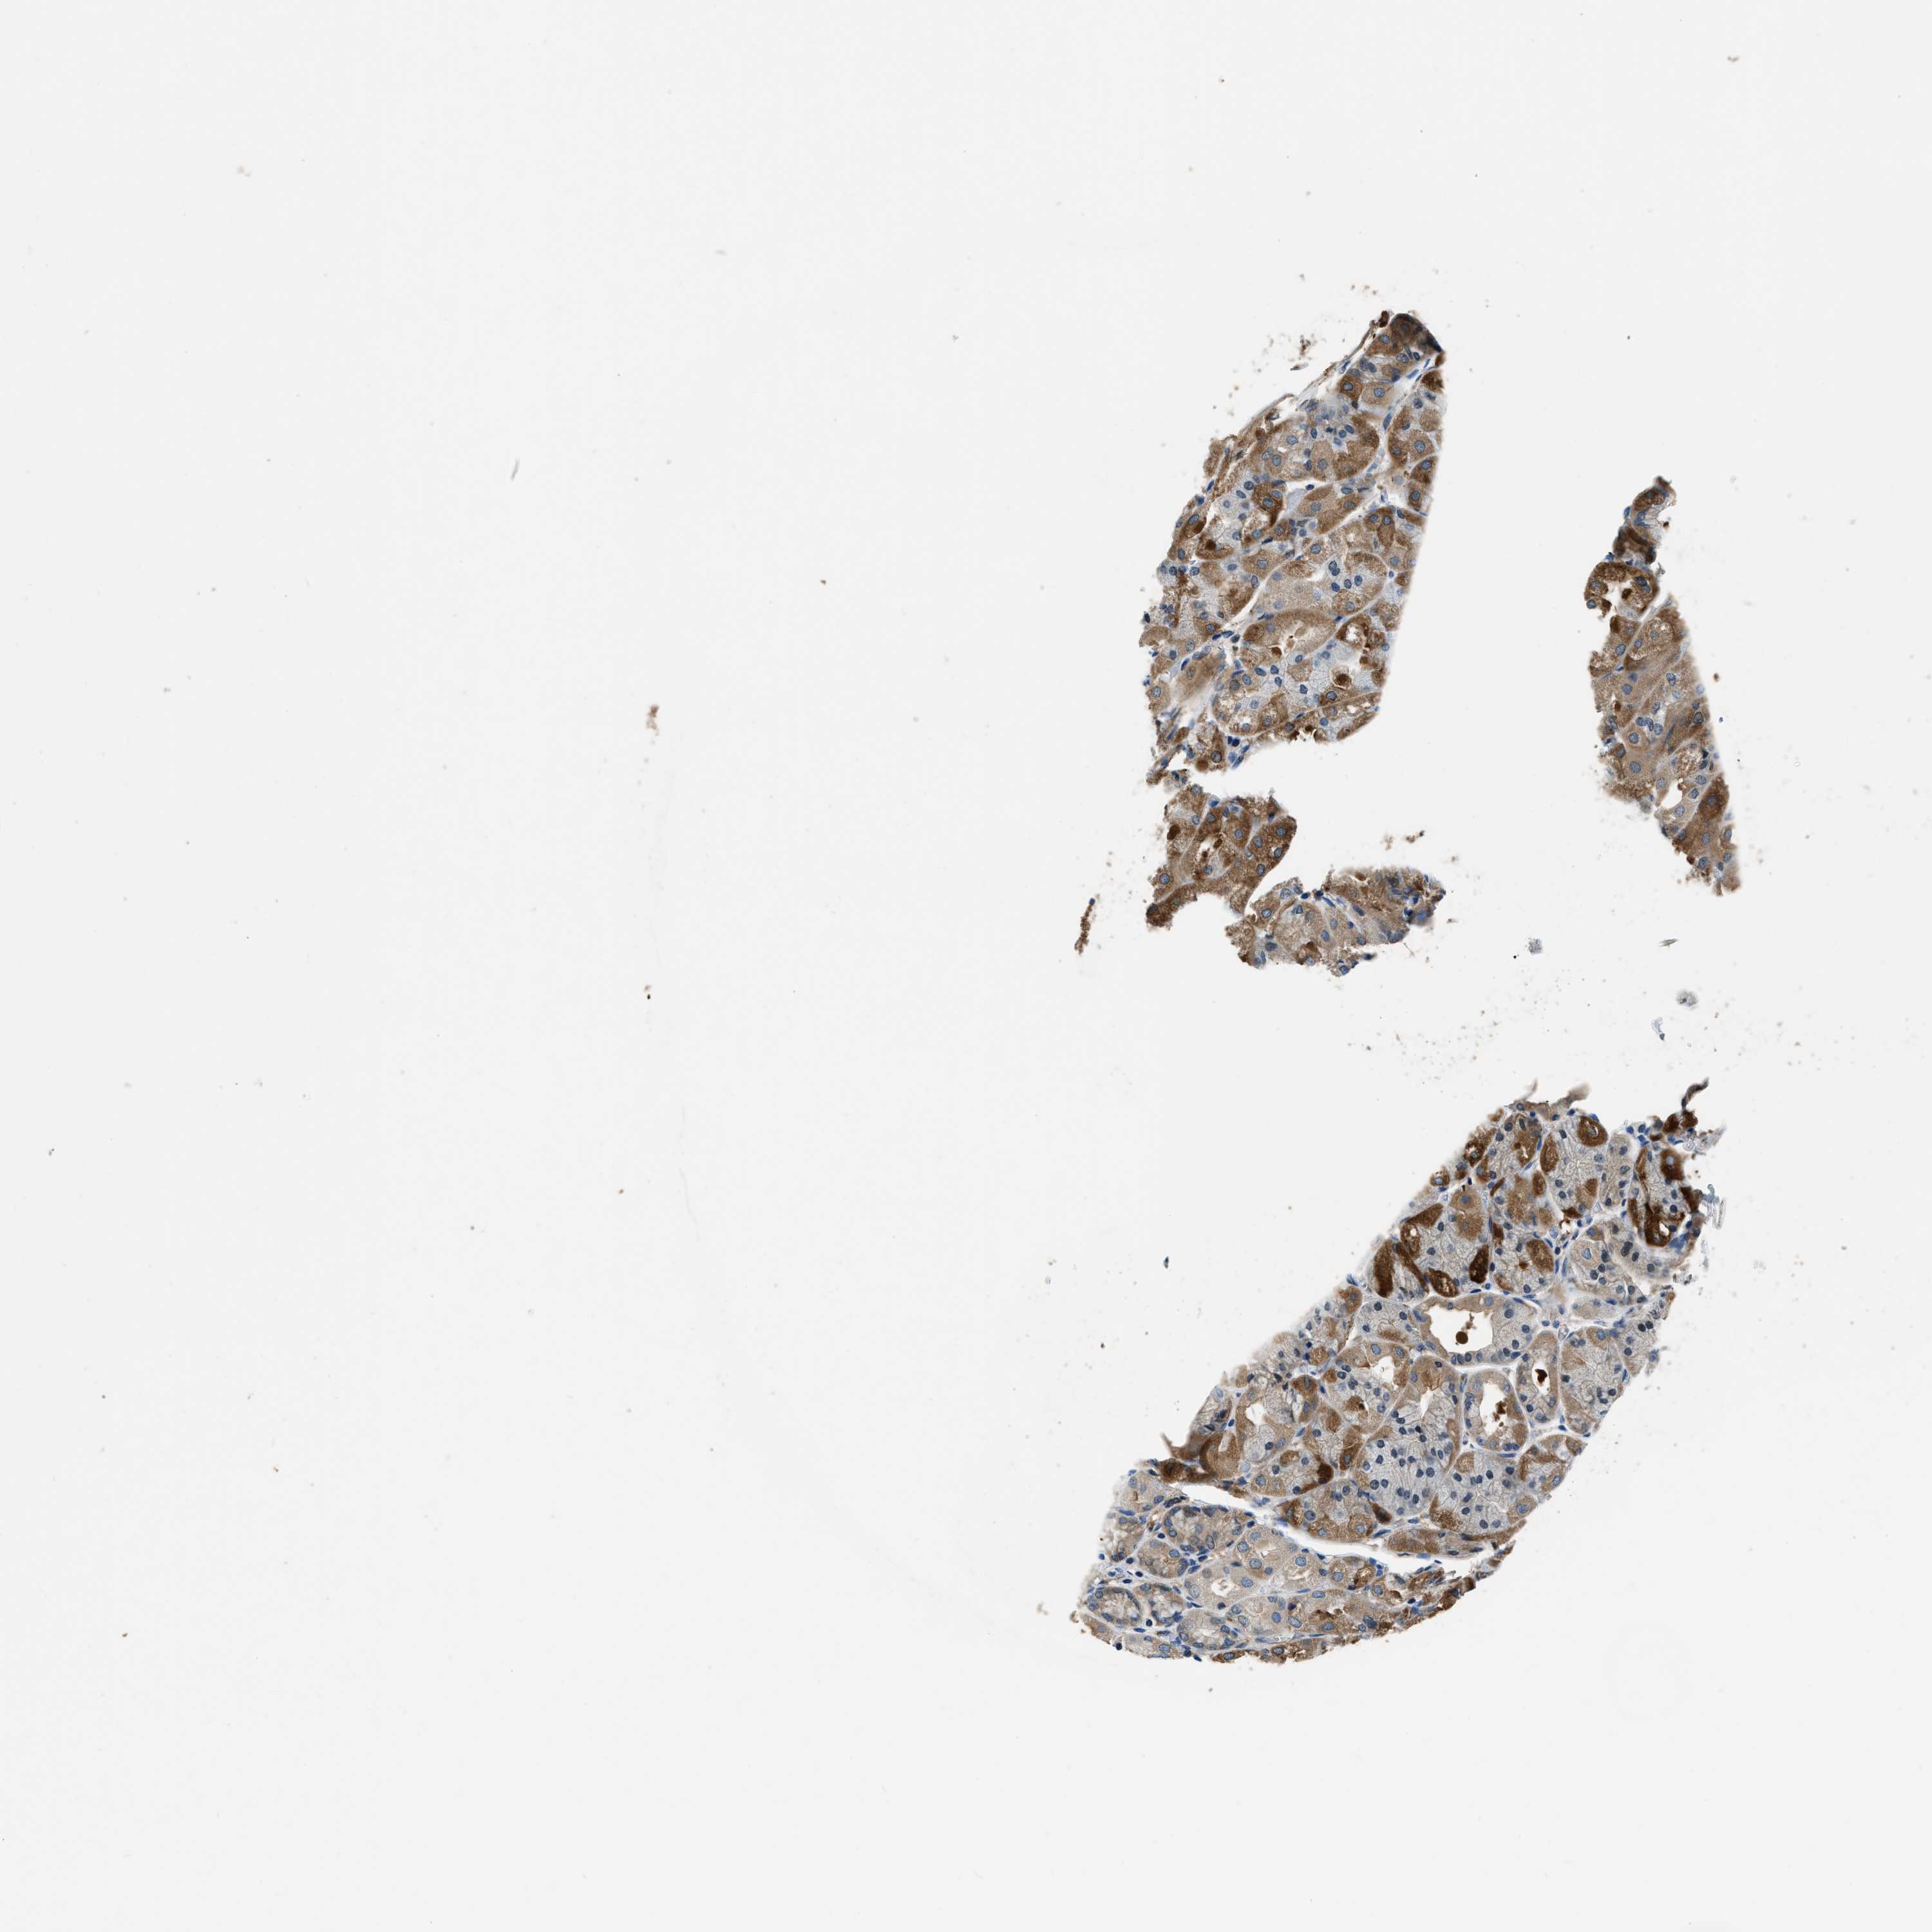

STOMACH 1 - Antibody stainingi

Antibody staining in the annotated cell types in the current human tissue is reported as not detected, low, medium, or high, based on conventional immunohistochemistry profiling in selected tissues. This score is based on the combination of the staining intensity and fraction of stained cells.

Each image is clickable and will lead to virtual microscopy that enables deeper exploration of all samples and also displays staining intensity scores, fraction scores and subcellular localization as well as patient and tissue information for each sample.

Antibody HPA018257

Glandular cells Medium